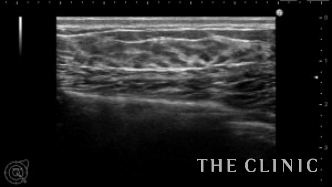

本日もヒアルロン酸のしこり除去です。

多発している場合は静脈麻酔で行いますが、ほとんどのヒアルロン酸のしこりは局所麻酔で行います。

その場で溶解して吸引するのですぐにしこりはなくなります。

両胸に大きなヒアルロン酸のしこりがありました。